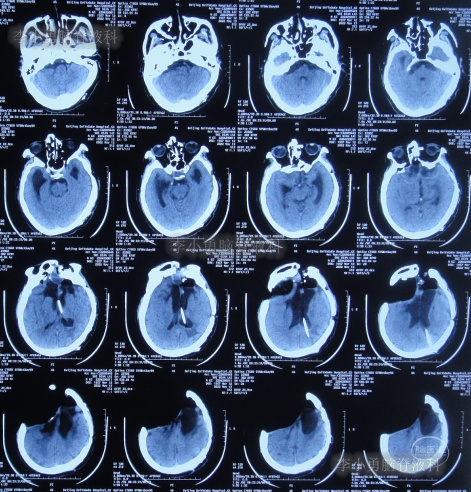

第3家医院出院后26天即2012年9月26日(开颅术后92天),因患者失语、嗜睡、吞咽障碍,第2次住入第3家医院,入院后2天即2012年9月28日,给予伤口及脑内脓肿清创缝合术+脑脊液漏修补术+右大腿取脂肪术,但术后2周即2012年10月12日,复查头颅CT提示脑积水(图-1)。

图-1:2012年10月12日头颅CT

2012年10月16日(第3家医院第2次住院20天),进行了脑室腹腔分流术(图-2)。

图-2:2012年10月16日头颅CT

脑室腹腔分流术后7天即2012年10月23日,患者突发意识丧失、双眼上翻伴头部抖动近20分钟后自行缓解,查头颅CT(图-3)后考虑为“颅内感染”。

图-3:2012年10月23日头颅CT

脑室腹腔分流术后11天即2012年10月27日,进行了脑室腹腔分流管腹腔端外置术(图-4),术中可见清亮脑脊液流出。

图-4:2012年10月27日头颅CT

治疗期间给予腰穿脑脊液检查未见细菌,但白细胞、蛋白偏高,体温仍间断升高,最高38.6度,期间查头颅CT示脑室仍有扩张(图-5)。

图-5:2012年10月30日头颅CT